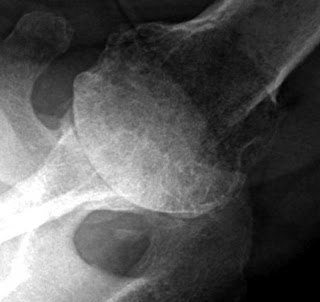

Here is an anteroposterior (AP) and an axillary view typical of shoulders with rotator cuff tear arthropathy.

The upper view, the AP shows the superior displacement of the humeral head, the superior glenoid erosion, the acromio-humeral contact, the concavity of the undersurface of the acromion, and the loss of the humeral tuberosities = femoralization of the humeral head and acetabularization of the glenoid and acromion.